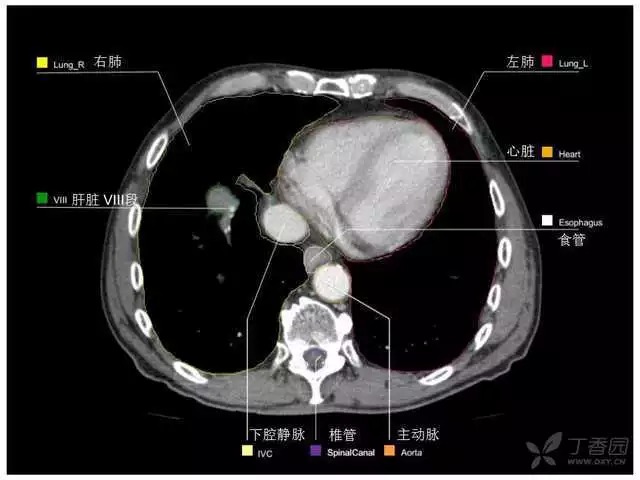

腹部肝脏高清CT断层的图谱

全腹部高清CT图谱,淋巴结彩色图谱,血管解剖图谱大汇总!

超声肝脏分叶及分段

肝脏分段和基本解剖学标志